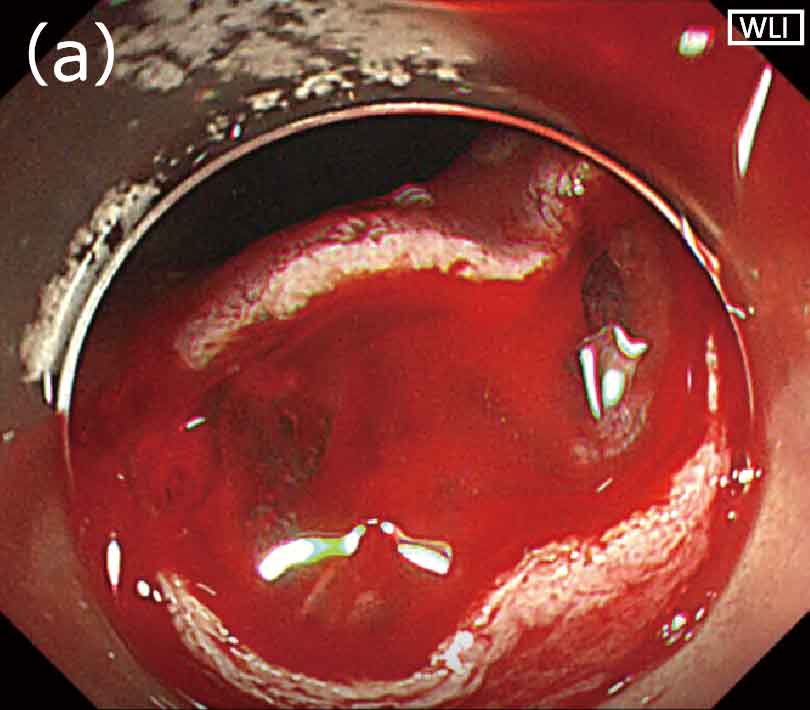

RDIモード下で微小出血であると確認した場合は、止血処置は行わずにESDを続行しています。静脈からの湧出性出血や小動脈からの出血と思われるような軽度の出血の場合(図3a)は、止血鉗子は使用せず格納したナイフ先端(DualKnifeJ)で接触凝固を行っています(図3b)。太めの動脈からの噴出性出血など、中等度から重度の出血の場合、従来の白色光観察では一瞬にして画面全体が赤くなってしまうことが多く、吸引や洗浄を行っても出血点の視認は困難でした(図4a)。しかしRDIモード下では、吸引や洗浄を行っている間に出血点が濃いアンバー色として描出されるため、容易に同定が可能です(図4b)。血液が多量に貯留した状態では、RDIモードに切り替えても、出血点の確認は困難となります。

〈図3〉RDIモード下での出血の程度の視認性(a)ナイフ先端で止血可能な軽度の出血;(b)閉じたナイフ先端を密着させての止血操作